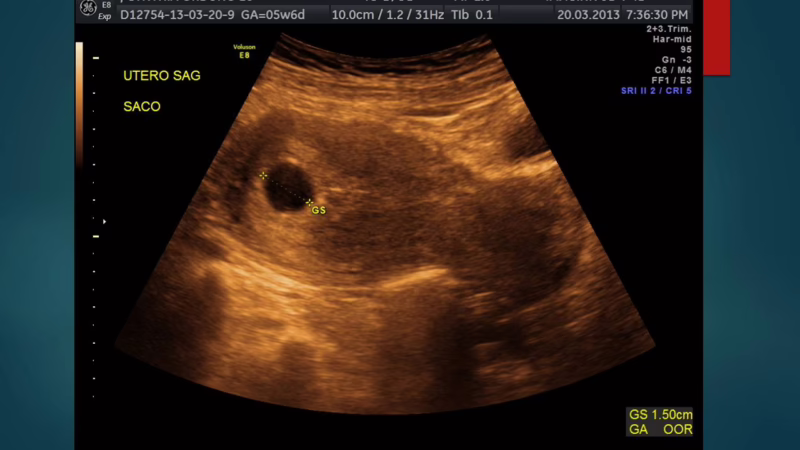

Saco gestacional

Uso del diámetro del saco gestacional para criterio de no viabilidad

•Criterio anterior:

•Diametro de 16 mm= No viabilidad

•Especificidad del 88-100%

•Criterio actual:

•Diametro de 25 mm= No viabilidad

•16-25 mm= Sospecha de no viabilidad

•La variabilidad entre exploradores es de